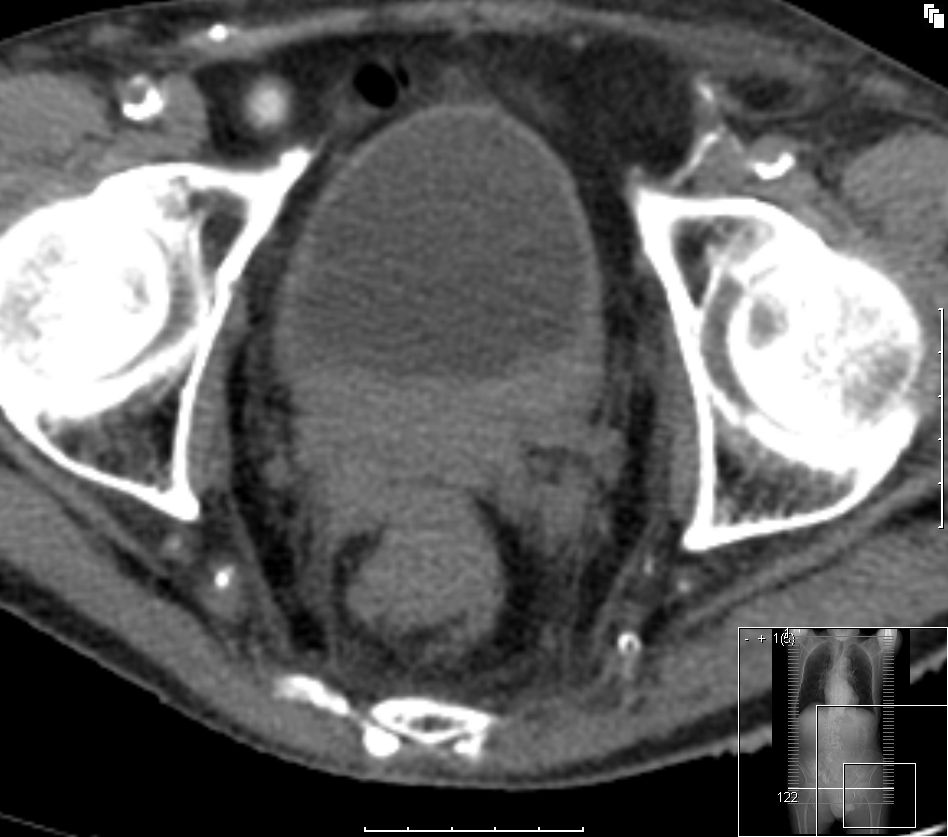

| primär metastasiertes Rektumkarzinom | CT-Bild eines stenosierenden

Rektumkarzinoms mit Infiltration der Hüllfaszie und Infiltration der

Prostatakapsel.![]() |